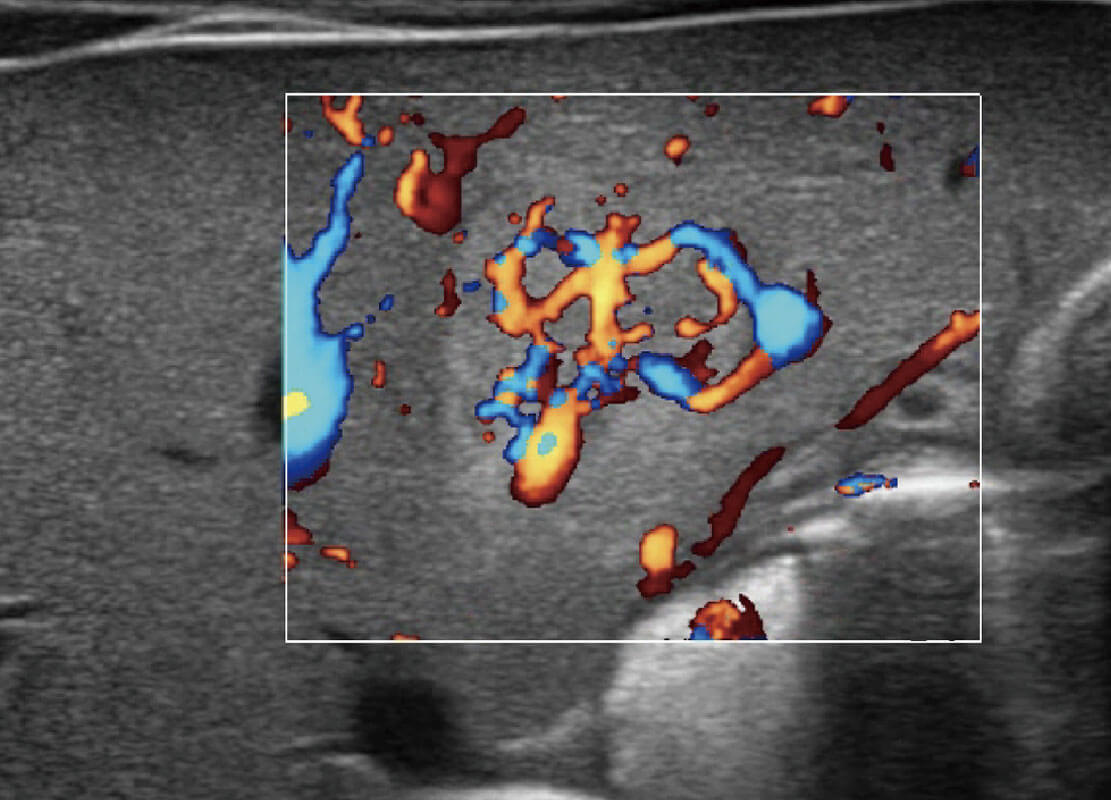

乳腺超声 / 新生儿

P60搭载宽频带线阵探头、宽景成像、弹性成像技术,为您提供乳腺应用方案。P60支持高频相控阵探头、线阵探头、腹部高频探头、腹部微凸探头等,丰富的探头群搭载敏感的彩色血流成像,适用于新生儿多种脏器检测要求,满足新生儿筛查需求。

• 新生儿肝血管癌

• 新生儿脊髓圆锥

• 新生儿心脏